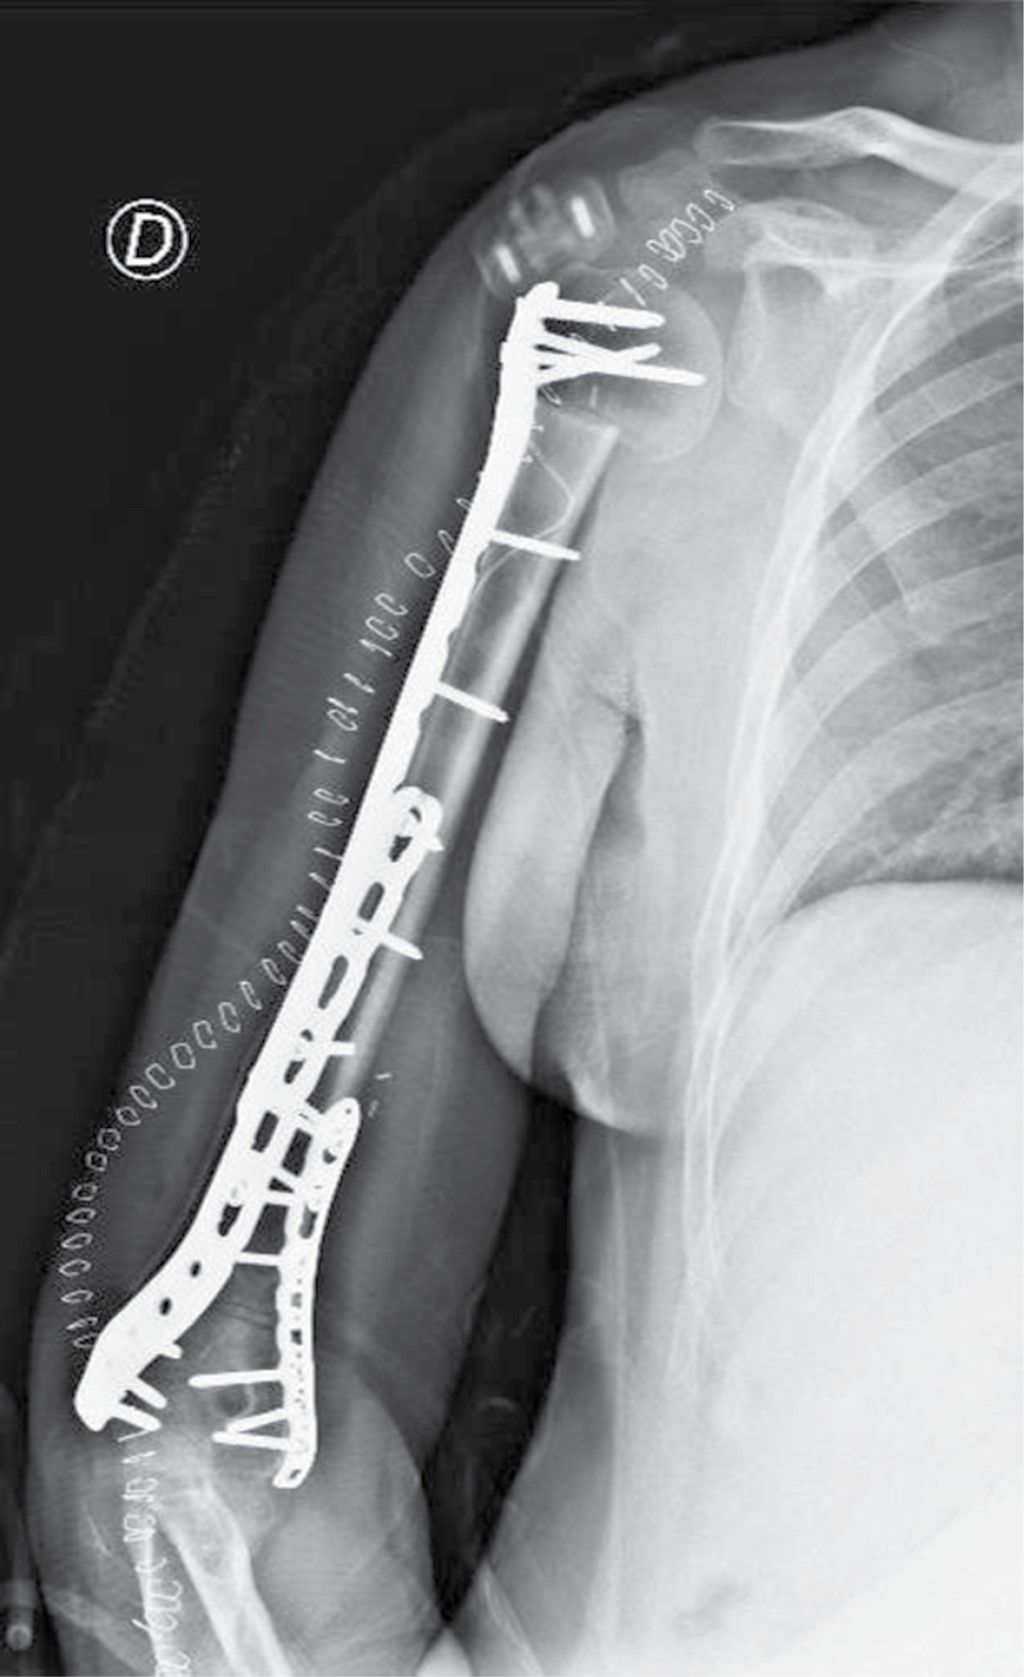

According to the surgical plan, the procedure was performed as follows. First, an expanded deltopectoral approach was performed, including the previous biopsy within the tumor lesion, curving toward the side and in the posterior and longitudinal directions over the olecranon. Subsequently, the tumoral lesion was dissected with wide lateral, middle and distal margins; at this level, the margin was close to the radial nerve, which was controlled along its entirety with neurolysis. Then, the deltoid muscle was dissected, exposing the axillary nerve, followed by tenotomy at the insertion points of the latissimus dorsi and pectoral muscles with complete dissection of the humerus, preserving the biopsy scar as part of the surgical specimen. Finally, osteotomy of the proximal humerus was performed at the level of the lower edge of the subscapularis muscle, and osteotomy of the distal supracondylar humerus was performed at the level of the olecranon fossa (Figure 4). Based on the MR images, adequate margins were obtained; then, frozen samples from the proximal and distal ends were examined and found to be negative. The defect was reconstructed with a massive allograft of the proximal humerus from the bone bank and proximal and distal fixation with plates and screws for osteosynthesis under adequate fluoroscopic control (Figure 5). Soft tissue reconstruction was performed by flap rotation and hemostasis followed by layered wound closure and skin stapling.

A control radiographic image was taken in the immediate postoperative period showing adequate congruence of the allograft with the host bones and fixation with the osteosynthesis material in the right humerus (Figure 6).

Figure 4

Figure 5

Figure 6